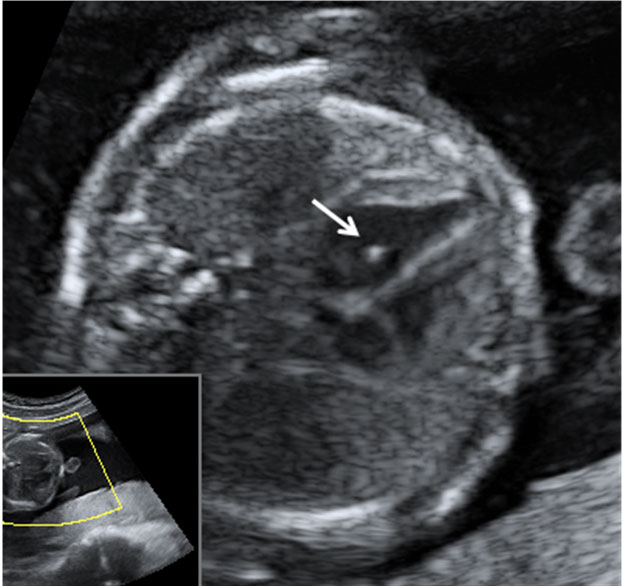

En la ecografía en 2D de la semana 20 de embarazo se hace un estudio pormenorizado de los órganos internos del feto y de su anatomía. Así se descubren muchas malformaciones congénitas, como en este caso, un pie equinovaro o zambo.